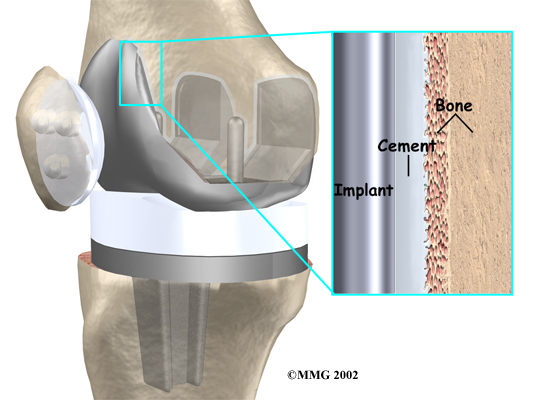

A cemented prosthesis is held in place by a type of epoxy cement that attaches the metal to the bone. An uncemented prosthesis has a fine mesh of holes on the surface that allows bone to grow into the mesh and attach the prosthesis to the bone.

The metal femoral component is then placed on the femur. In the uncemented prosthesis, the metal piece is held snugly onto the femur because the femur is tapered to accurately match the shape of the prosthesis. The metal component is pushed onto the end of the femur and held in place by friction. In the cemented variety, an epoxy cement is used to attach the metal prosthesis to the bone.

The metal tray that holds the plastic spacer is then attached to the top of the tibia. This metal tray is either cemented into place, or held with screws if the component is of the uncemented variety. The screws are primarily used to hold the tibial tray in place until bone grows into the porous coating. (The screws remain in place and are not removed.)